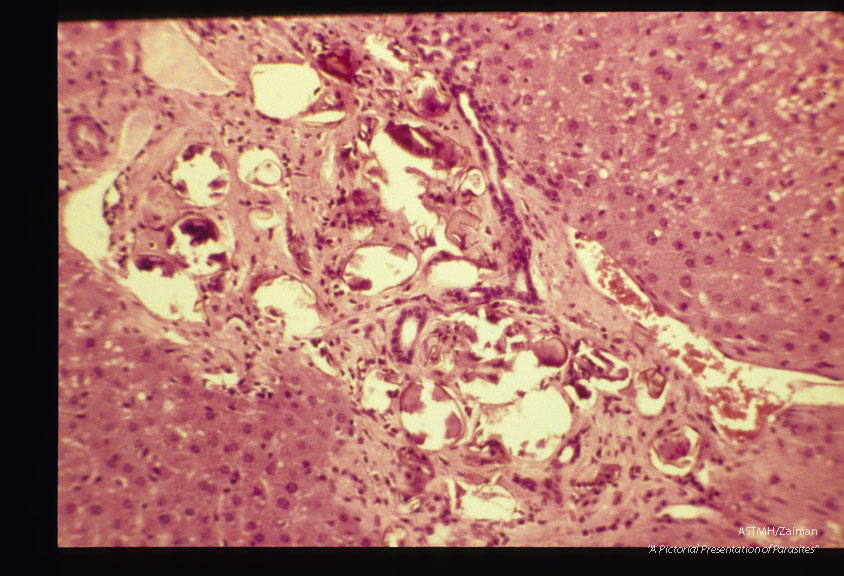

Eggs in armadillo (Dasypus novemcinctus) liver.

Heterobilharzia americana?

Description: Eggs in armadillo (Dasypus novemcinctus) liver.